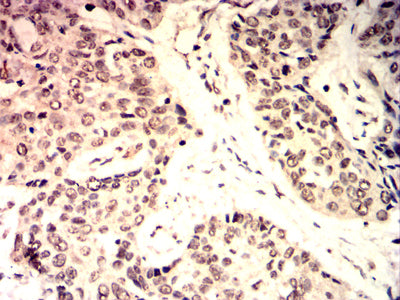

Immunohistochemical analysis of paraffin-embedded human esophageal cancer tissues using C-MYC mouse mAb with DAB staining.

Immunohistochemical analysis of paraffin-embedded human lung cancer tissues using C-MYC mouse mAb with DAB staining.